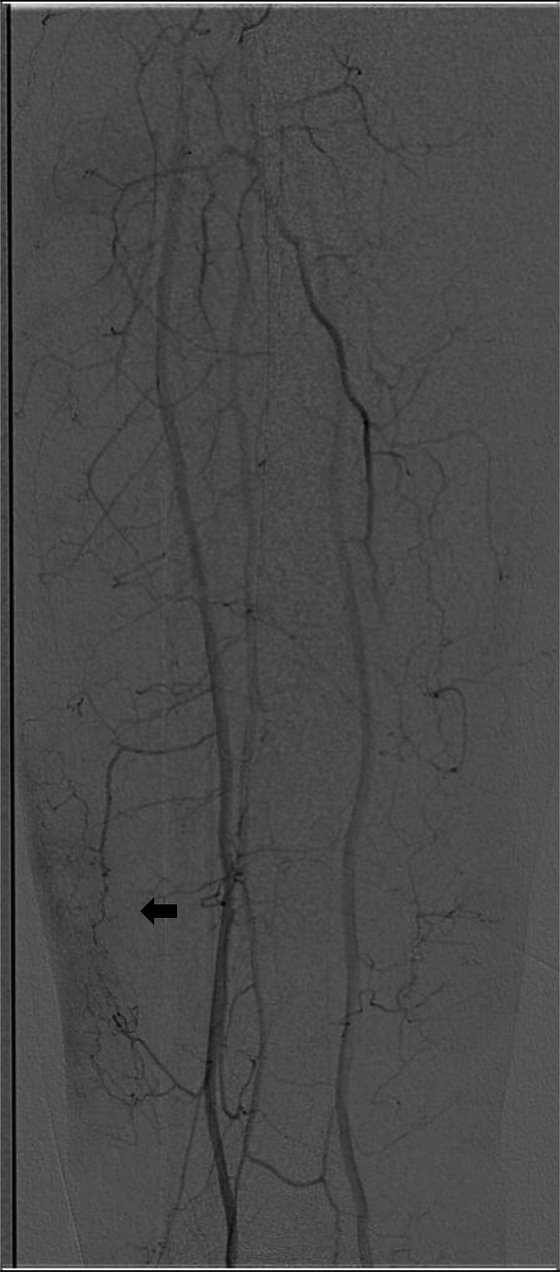

经动脉微栓塞(TAME)已被公认为慢性肌肉骨骼疼痛的微创治疗方法,具有显著的疗效和良好的安全性(1,2)。然而,并发症的报道仍然不足。本病例报告描述了第一个记录严重不良事件的患者慢性静脉溃疡接受TAME微动静脉瘘(AVF)。患者出现了明显的并发症,包括广泛的腿部肿胀、皮肤变化和蜂窝织炎,需要长期住院治疗。这些发现强调了患者选择和栓塞剂考虑的重要性,以减轻与TAME相关的潜在风险。

Transarterial microembolization (TAME) has gained recognition as a minimally invasive treatment for chronic musculoskeletal pain, demonstrating significant efficacy with a favorable safety profile ( 1, 2). However, complications remain underreported. This case report describes the first documented severe adverse event in a patient with a chronic venous ulcer undergoing TAME for a micro arteriovenous fistula (AVF). The patient developed significant complications, including extensive leg swelling, skin changes, and cellulitis requiring prolonged inpatient care. These findings highlight the importance of patient selection and embolic agent considerations to mitigate potential risks associated with TAME.